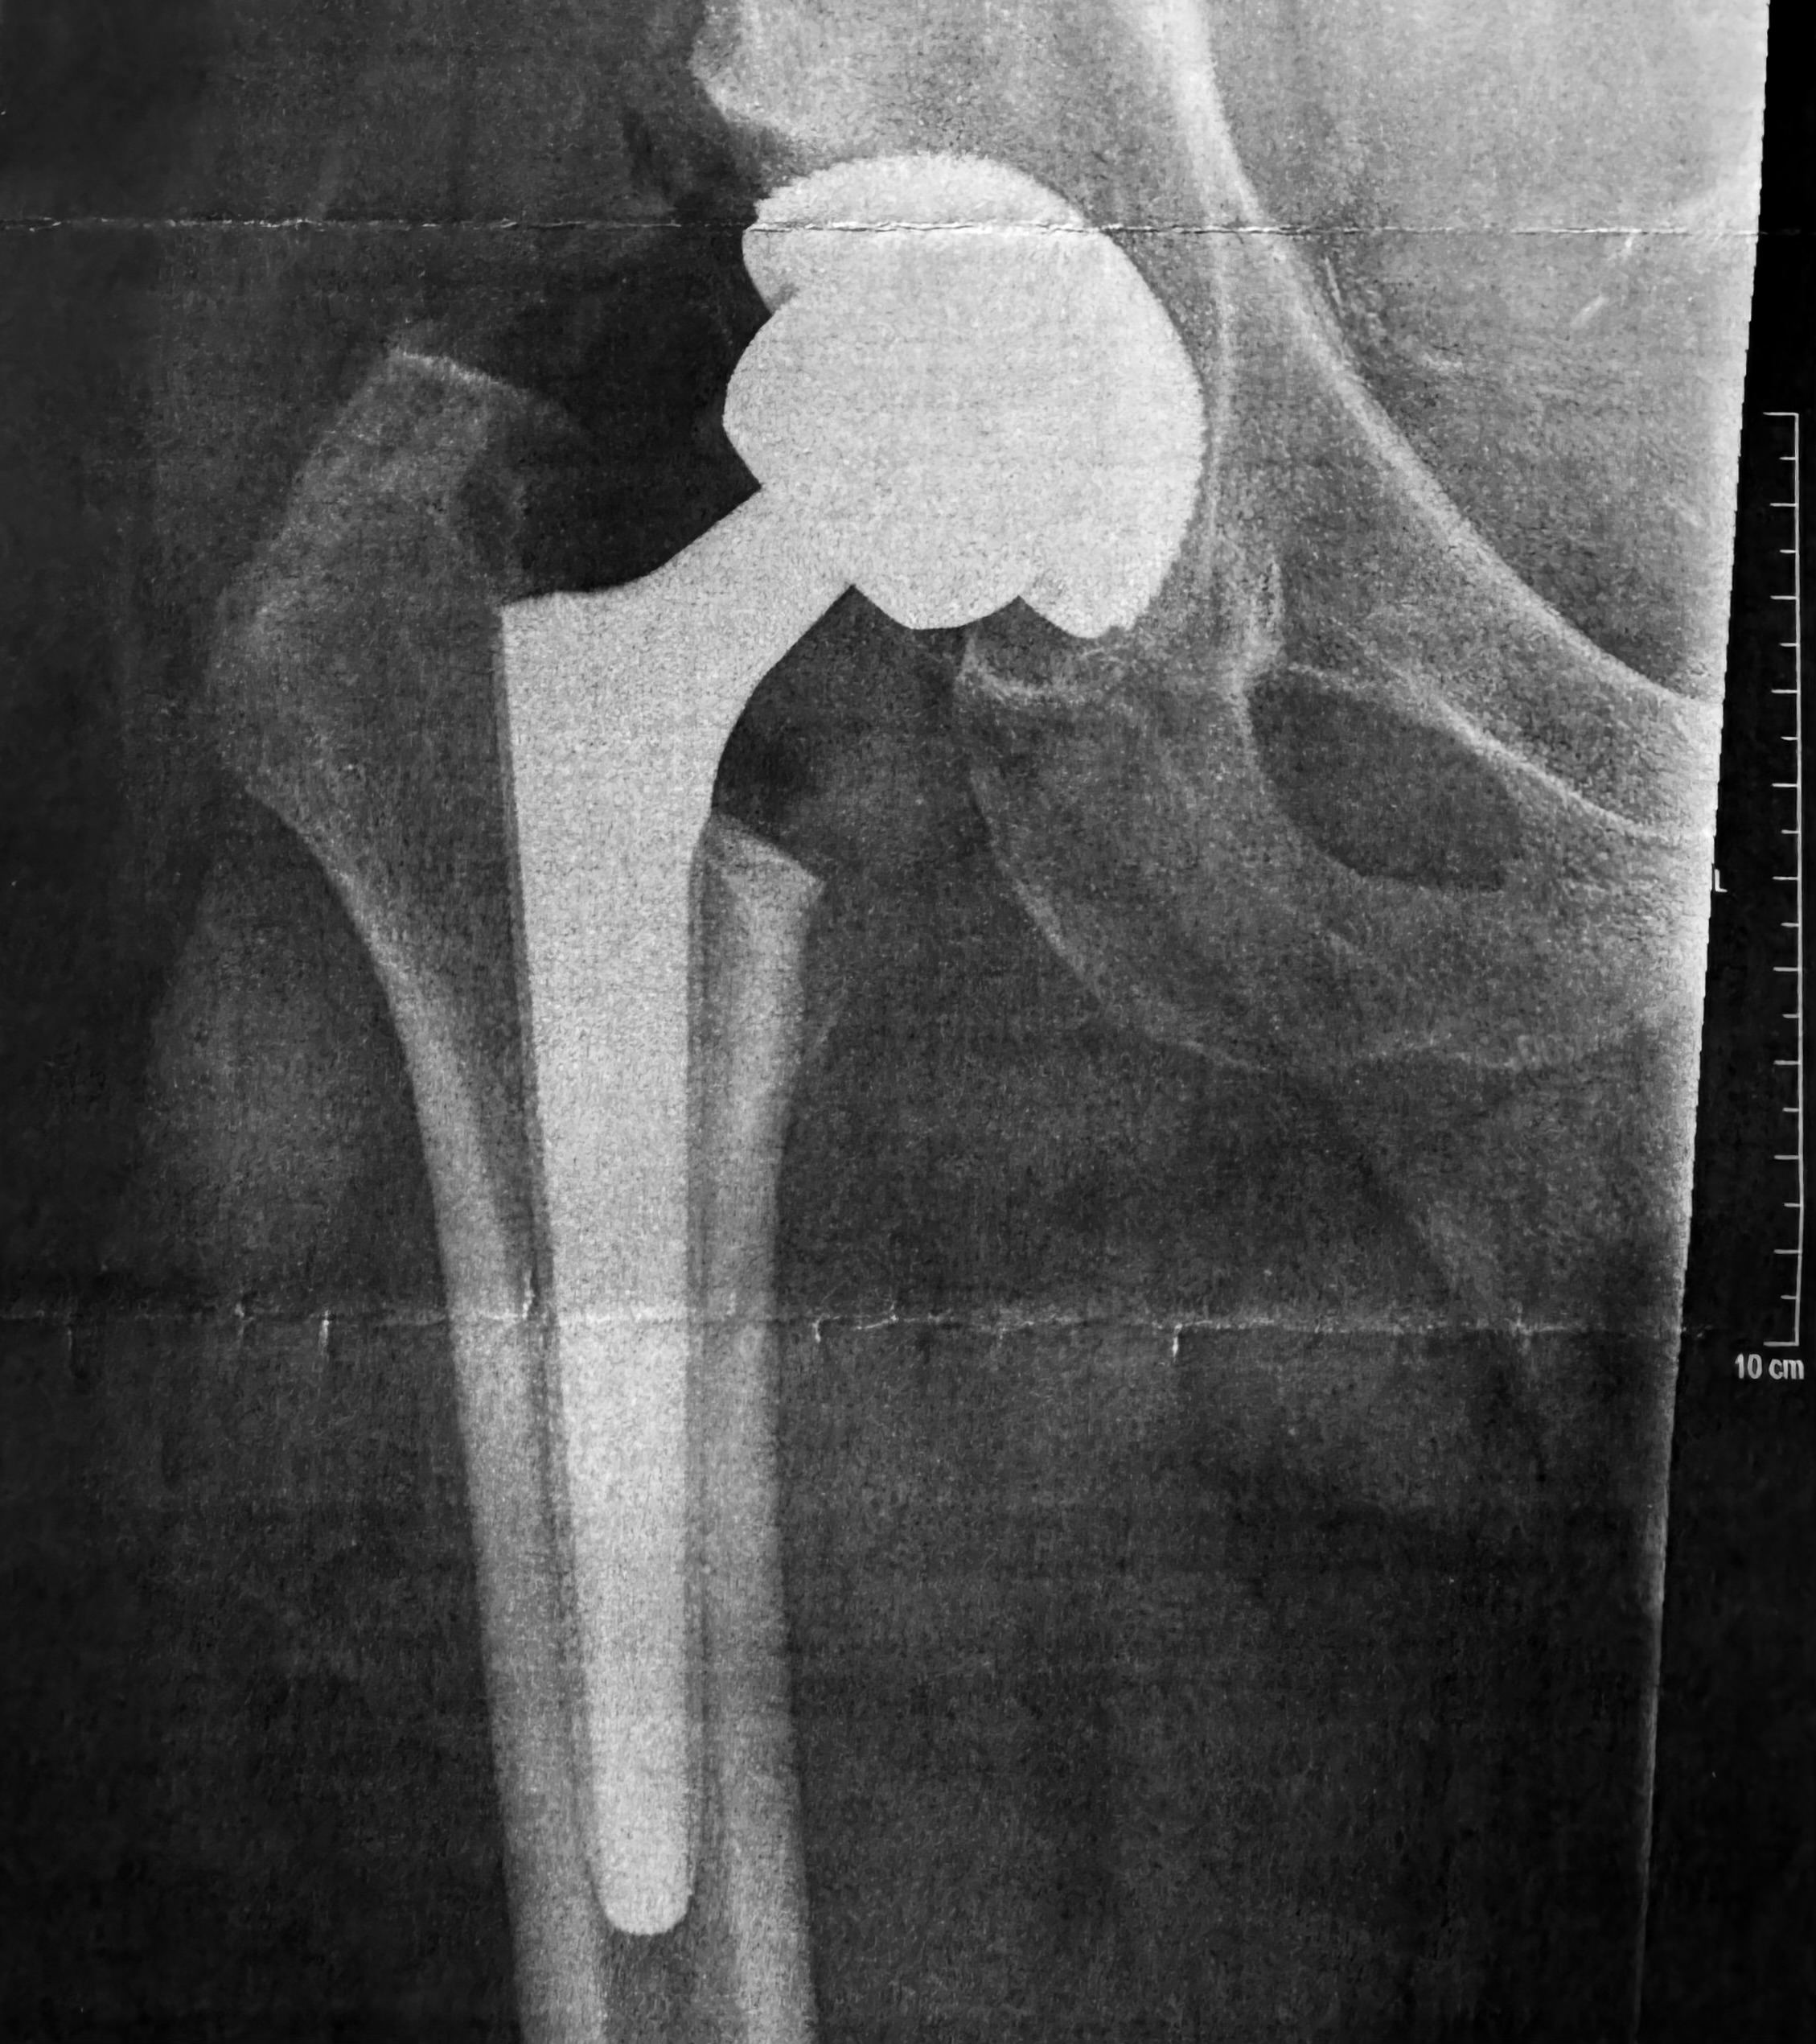

Ende 2025 war es dann soweit. Meine Wahl fiel auf die VITREA Ostseeklinik Damp (ehemals VAMED / Damp 2000). Und wenn ich mir meinen OP-Bericht heute ansehe, weiß ich, dass ich dort in den Händen absoluter Profis war. Denn das war keine „Standard-Hüfte“.

Der Bericht liest sich wie ein handwerklicher Krimi. Die Diagnose lautete: Fortgeschrittene sekundäre Koxarthrose bei Dysplasie und Z. n. Perthes. Auf Deutsch: Mein Gelenk war nicht nur verschlissen, es war durch die Kinderkrankheit auch völlig falsch geformt.

Was die Operateure vorgefunden haben:

- Massive Verformungen: Der Hüftkopf war „komplett entrundet und abgeplattet“, dazu riesige „Osteophyten“ (Knochenwucherungen), die sich über die Jahre gebildet hatten.

- Verkürzte Muskeln: Ein wichtiger Muskel für die Hüftdrehung, der Piriformis, war „komplett verkürzt und teilweise atroph“ (geschrumpft). Er musste während der OP durchtrennt werden, damit das neue Gelenk überhaupt bewegt werden kann.

Trotz dieser extremen Ausgangslage dauerte die OP deutlich weniger als 2 Stunden. Über einen nur ca. 12 cm langen Schnitt wurde mein altes, deformiertes Gelenk entfernt. Es ist faszinierend: Da der Knochenkanal in meinem Oberschenkel sehr eng („zugewachsen“) war, mussten die Chirurgen extrem präzise arbeiten, um den Knochen nicht zu spalten.

Das Hightech-Material in meinem Körper: Eingebaut wurde eine Wagner Conus Prothese (Größe 19) aus Titan, die speziell für solche schwierigen Knochenverhältnisse gemacht ist. Dazu kam eine Allofit IT Pfanne von Zimmer und ein 36mm Keramikkopf. Diese Kombination aus Keramik und modernem Kunststoff (Inlay) verspricht extrem lange Haltbarkeit.

Aber ich bin nicht schmerzfrei, und ein Blick in den OP-Bericht erklärt auch, warum das so sein muss. Vor der OP hatte ich eine Beinverkürzung von fast 5 cm. Mein Körper hatte sich über Jahrzehnte schiefgezogen. Durch die OP konnten die Ärzte das Defizit auf ca. 1 cm reduzieren. Das bedeutet, mein Bein wurde in einer einzigen Sitzung um mehr als 3 Zentimeter verlängert!